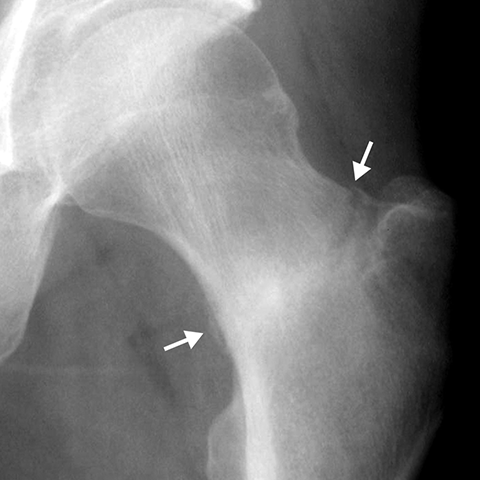

Fracture of Femoral Neck